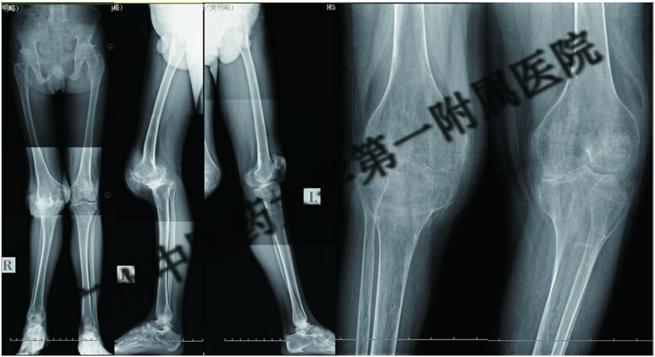

图2.髋膝关节僵直,髌骨脱位,严重骨质疏松

图3.患者髋、膝、踝关节僵直导致残疾